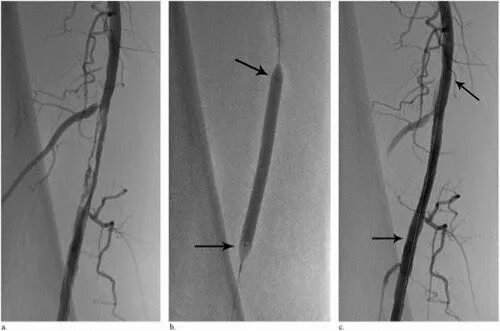

После стентирования какие